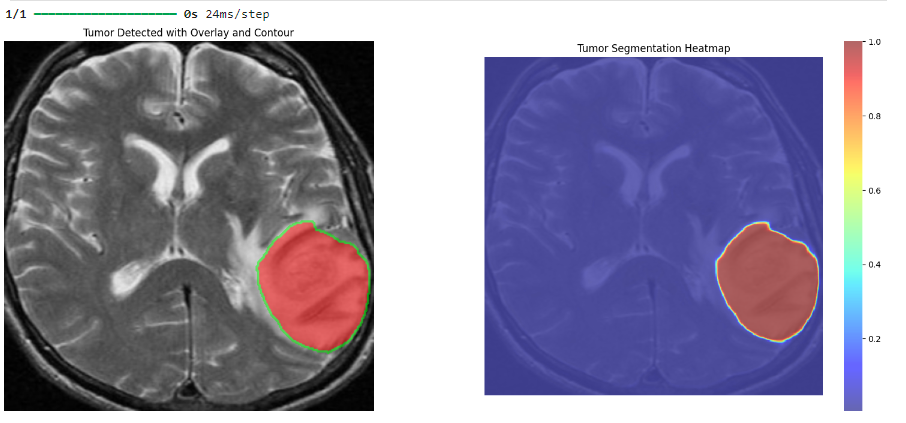

Revolutionizing Brain Tumor Detection with Deep Learning (FYP) 2024-09-01

Project focuses on the development of a robust and accurate system for detecting brain tumors from MRI scans using advanced deep learning techniques. The core of the project leverages Convolutional Neural Networks (CNN) and U-Net models to achieve high precision in tumor identification and segmentation.